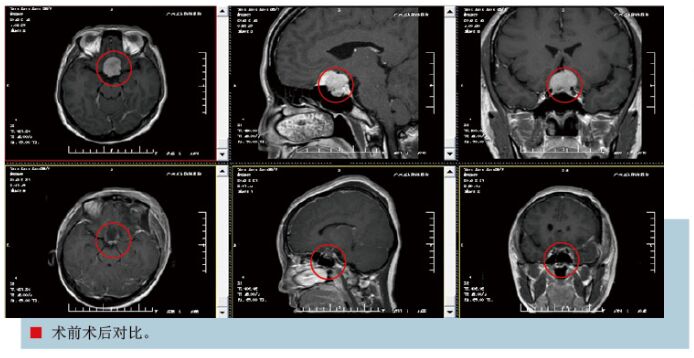

患者黄某,男性,52岁,因“视力逐步下降10月余”于2015年5月16日收治入院,2015年6月8日出院,共住院23天。患者于2014年7月份无明显诱因出现视力下降,无头痛头晕、恶心呕吐,无四肢抽搐,无发热,遂就诊当地医院行头颅MR示:鞍区占位性病变,考虑垂体腺瘤或脑膜瘤可能性大。入院查体:生命体征平稳神志清楚,对答切题。双瞳孔等大同圆,直径2.5mm,对光反射灵敏,双侧眼球活动自如,右侧视力1米数指,左侧视力0.5,余脑神经体查未见异常,步态稳健,四肢肌力5级,肌张力正常,全身深浅感觉体查未见异常,生理反射存在,病理征未引出。辅助检查头颅MR示:鞍区占位性病变,考虑垂体腺瘤或脑膜瘤可能性大。入院诊断:鞍区占位性病变:脑膜瘤可能性大。入院后完善相关检查,于2015年5月25日在全麻下行“鞍区占位性病变切除术”,术程顺利,给予营养神经等治疗,视力逐渐恢复,出院时双眼视力均为0.5,一般情况好。复查头颅CT、MRI示:呈术后改变,未见肿瘤增强信号。术后病理结果回报:脑膜瘤。